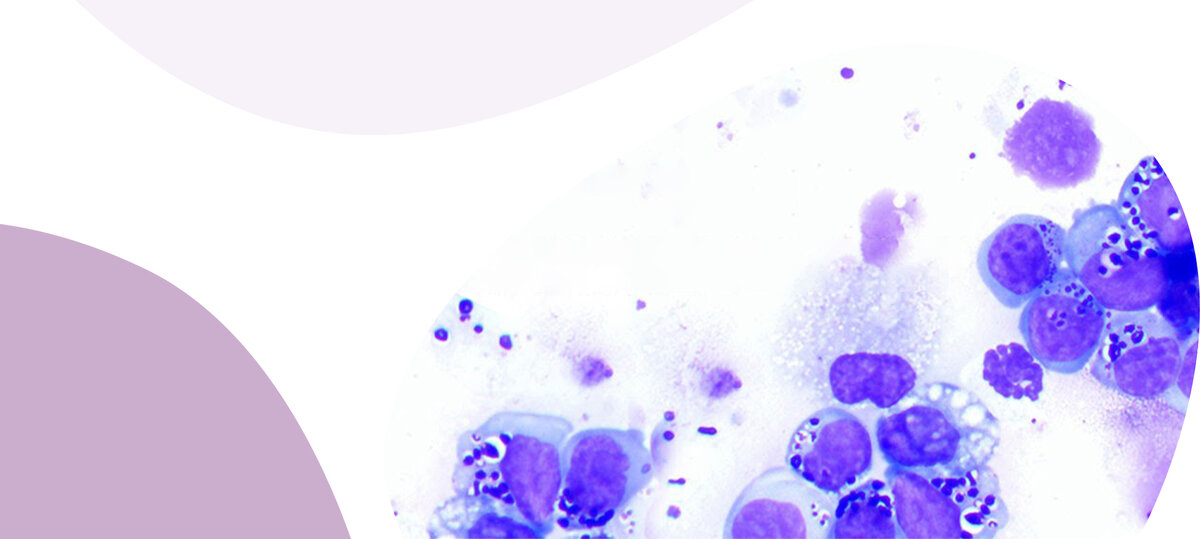

Крупноклеточная гранулярная лимфома

Пациент – кошка

Лимфома – злокачественное опухолевое заболевание лимфатической системы. Один из самых распространенных типов рака у кошек.

В рамках цитологического исследования проводится диагностика пораженных лимфоузлов, определяется причина их увеличения и наличие в них опухолевых клеток.